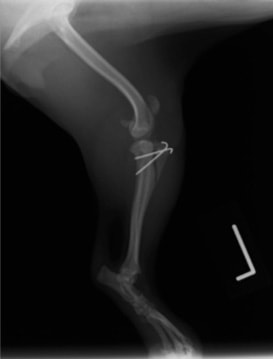

■ 症例20 ポメラニアン 8ヶ月 1.8kg

左右膝蓋骨脱臼 グレードⅢ

2ヶ月前から間欠的跛行が認められ、両膝の膝蓋骨脱臼整復術を行った。

手技は縫工筋及び内側広筋の解放、脛骨粗面の外側転位、滑車ブロック形造溝術、内外側関節包の縫縮を選択し実施した。

右側の膝蓋骨脱臼は上記手技で整復されたものの、左側はそれのみでは膝蓋骨が浮く様子が認められた。その為、PDS縫合糸にて膝蓋靱帯を1糸のみ縫合し、靱帯の縫縮を行った。

膝蓋骨脱臼は膝関節における膝蓋骨の内外側の脱臼と定義されるが、時として単純な内外の脱臼ではなく、膝蓋骨が大きく前方に浮き上がるように脱臼する場合がある。特にトイプードルやポメラニアンといった犬種に多く認められる。

内側脱臼に加えて前方への浮き上がりを矯正する為に、従来より脛骨粗面転移により膝蓋靭帯を外方と下方に引っ張り、固定する方法を選択する。膝蓋骨の前方への浮き上がりが軽度の場合は、従来法ではなく関節包の縫縮で対応していた。しかし、一部の症例で膝蓋骨の動きが悪くなり伸展機構が円滑に機能せずロボット様歩行になるケースがあった。

その為、膝蓋靭帯自体を縫縮する方法を採用した。この方法により、膝関節の伸展機構を妨げず膝蓋骨の軽度の浮きを矯正することが可能となった。

本症例の経過は良好である